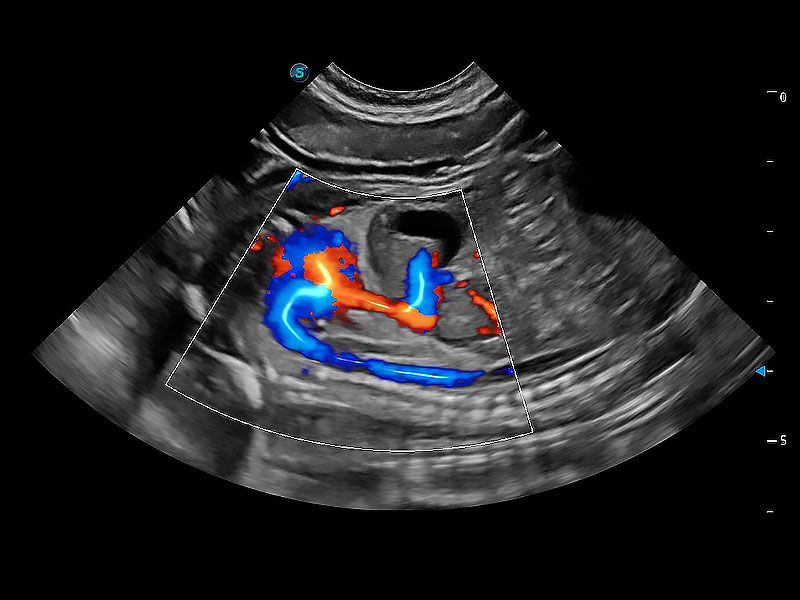

ProPet 80 配备了丰富的心脏探头群、先进的成像技术和专业的心脏测量工具,可帮助动物医生为不同体型和生理结构的动物提供心脏和心肌功能的全面评估。

通过心肌识别技术与二维斑点追踪技术相结合,对心脏的超声图像进行量化分析。计算心肌17个节段的应变、应变率、速度、位移等,并通过牛眼图的形式进行呈现。

通过360度任意调节3条M型取样线,在同一心动周期上观察心脏不同位置的运动曲线,得到准确的心功能测量数据,有效评估心肌运动及左心室功能。

能够基于左心室壁追踪和辛普森法,自动计算射血分数,支持多个可移动点描迹,与手动测量相比,极大节省了动物医生的时间和精力。